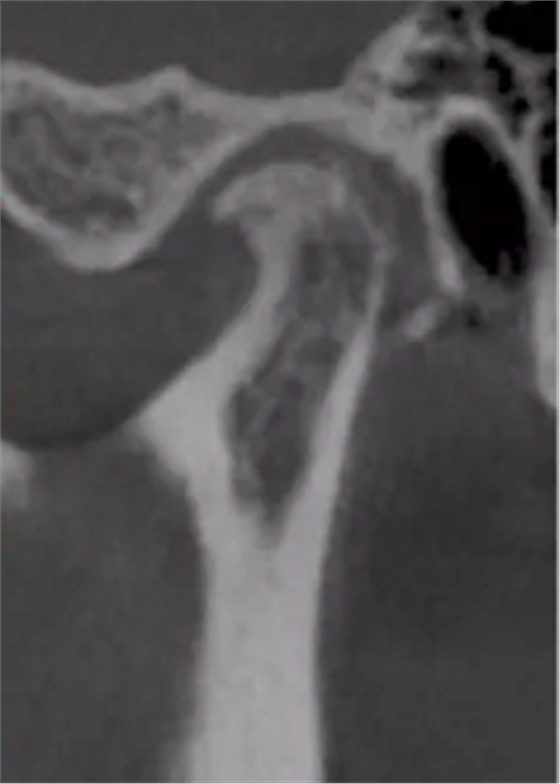

更嚴重的是會影響下頜關(guān)節(jié)的健康,正常下頜運動三模式開口運動,側(cè)方咬合,前伸下頜,閉鎖合時只留開口運動模式了,其他二種只有先開口后才能發(fā)生。這樣由于上前牙內(nèi)傾,強迫下頜后退,使下頜關(guān)節(jié)位置異常,關(guān)節(jié)頭越磨越平。這類人群往往有關(guān)節(jié)區(qū)疼痛、張閉口彈響,張不開口等,嚴重的會影響日常生活和情緒。

關(guān)節(jié)頭損傷